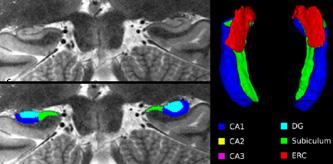

b) a) c) The Tic-Tac-Toe (TTT) radiofrequency head coil for 7T MRI Fig 1: in a), the implemented 16-channel TTT transmit RF coil; in b), the computational RF coil in c), the implemented RF coil with an 32-channel receive insert Fig. 2: The B1+ (magnetic field responsible for spin excitation) field homogeneity is highly degraded at 7T MRI due to a higher operational frequency (~297MHz). The TTT presents a more homogeneous field distribution when compared with the NOVA coil (a commercial coil) [1]. Measured Tic-Tac-Toe Measured Nova coil Regions with low B Simulated Tic-Tac-Toe B + maps in the brain: TTT vs NOVA RF coils TTT coil NOVA coil TTT coil NOVA coil Image comparison with the 32-channel NOVA commercial RF coil a) b) Fig. 3: In a), Turbo spin echo (TSE) sequence using the TTT coil with resolution of 0.4x0.4x2mm. In b), the same TSE sequence acquired with the commercial NOVA coil. In c), FLAIR sequence acquired with TTT coil with resolution of 0.7x0.7x2mm. In d), the same FLAIR sequence acquired with NOVA coil. The arrows point to regions of dark spots in the NOVA coil images and compare with similar regions on the TTT coil images [1]. c) d) High-resolution susceptibility weighted images showing cortical microvessels Fig 4 SWI images acquired at 0 2x0 2x1 5mm resolution In a) an axial slice of the whole brain image acquisition In b) and c), zoomed versions of a), detailing the micro-structures a) b) c) High resolution angiography without contrast agents 380μm a) b) Fig 5: Maximum intensity projection orientation and small vessels detectability isotropic image showing whole brain isotropic acquisition In d), 0 20mm are only detectable at higher resolution

Finger tapping task: activation of Functional MRI a) Diffusion MRI and fiber tracking Post-mortem a) a) b) Fig 7 In a), an structural MPRAGE image acquired at 0 75mm isotropic (skull removed using FSL package) In b), fiber tracking based on DTI acquisition, 64 directions, 1 5mm isotropic resolution The colors are defined for different orientations of the fibers Fig 8: In a), susceptibility weighted images acquired at 0 35mm isotropic, 32 min acquisition time, in a post-mortem brain fixated with formalin In b), a photograph of similar slice in the same brain Table 1: 7T MRI studies conducted at the RF Research Facility at University of Pittsburgh White matter legions (circle): Multiple Sclerosis study Stroke (circle): sickle cell disease study Automatic hippocampus segmentation: Midlife Neurocognitive Lacunar infarct (arrow): depression study White matter hyperintensities (arrows): Healthy Brain aging study (left) and Small Vessels disease in preclinical Alzheimer’s disease study (right) Fig 9: Sample of some studies listed in Table 1 using the developed 16 array (Fig a) There are 4 completed studies and 13 ongoing patient studies with approximated 2 000 patients scheduled FUTURE DIRECTIONS 64-channel Tic-Tac-Toe RF transmit coil for 7T MRI 0 Fig 10: In a), the 64-channel transmit coil computational modeling [2] To improve the field of view of the projector/monitor in fMRI studies, the frontal panels can be removed, resulting in a 56-channel coil In b), one assembled side of the coil In c), simulated B1+ field distribution: for an 8kW power amplifier capabilities (default in older 7T MRI scanners) a homogeneity (measured by the coefficient of variationCV) of 15 2% is achieved in the brain For an 16 kW power amplifier (available for the recently FDA approved Siemens 7T MAGNETOM Terra), an CV of 10 6% can be achieved in the brain 16 kW power amplifier: 8 kW power amplifier: a) b) c) max